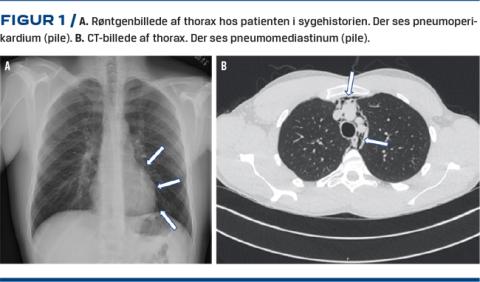

En CT af thorax viste efterfølgende bilateral pneumothorax med apikale spalter på hhv. 1,5 cm og 8 mm, udtalt pneumomediastinum og pneumoperikardium (Figur 1).